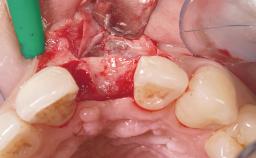

A 33-year-old female patient presented with an upper left central incisor that required extraction after a failed endodontic therapy. The tooth had been traumatized when the patient was a teenager and had undergone several endodontic treatments, including two apicectomy procedures. The patient was in good health and did not smoke. Clinical examination showed that the patient had a high lip line. In full smile, the gingival margins of the upper teeth were visible to the first molars. The gingival margins of central incisors 11 and 21 were only just showing. Examination of tooth 21 confirmed that the tooth was mobile and had hypererupted by 1 mm.

Soft Tissue Grafting Simultaneous

Soft Tissue Anatomy Intact Defective

Placement Protocol Immediate implant placement